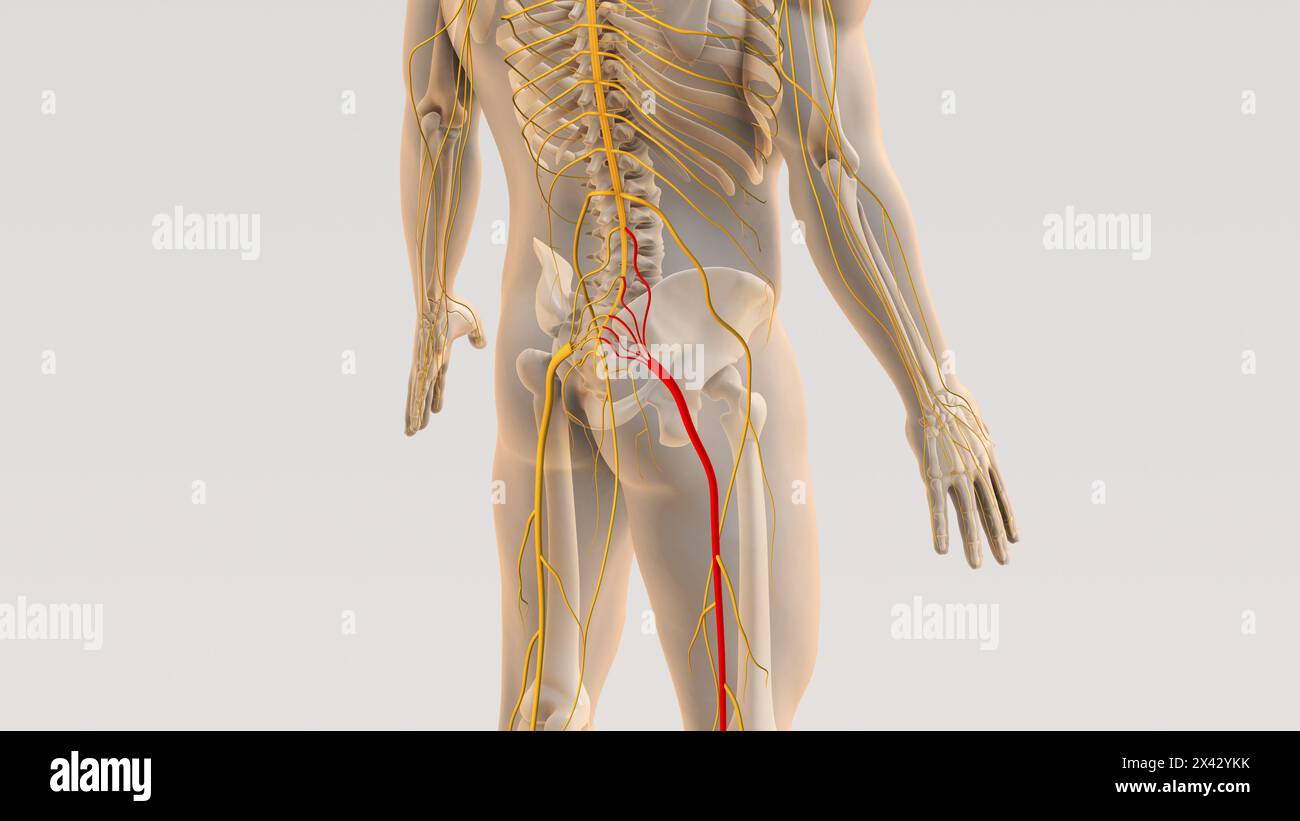

Ischiaswirbelsäule und Nervenschmerz medizinisches Konzept Stockfotohttps://www.alamy.de/image-license-details/?v=1https://www.alamy.de/ischiaswirbelsaule-und-nervenschmerz-medizinisches-konzept-image604887127.html

Ischiaswirbelsäule und Nervenschmerz medizinisches Konzept Stockfotohttps://www.alamy.de/image-license-details/?v=1https://www.alamy.de/ischiaswirbelsaule-und-nervenschmerz-medizinisches-konzept-image604887127.htmlRF2X42YKK–Ischiaswirbelsäule und Nervenschmerz medizinisches Konzept